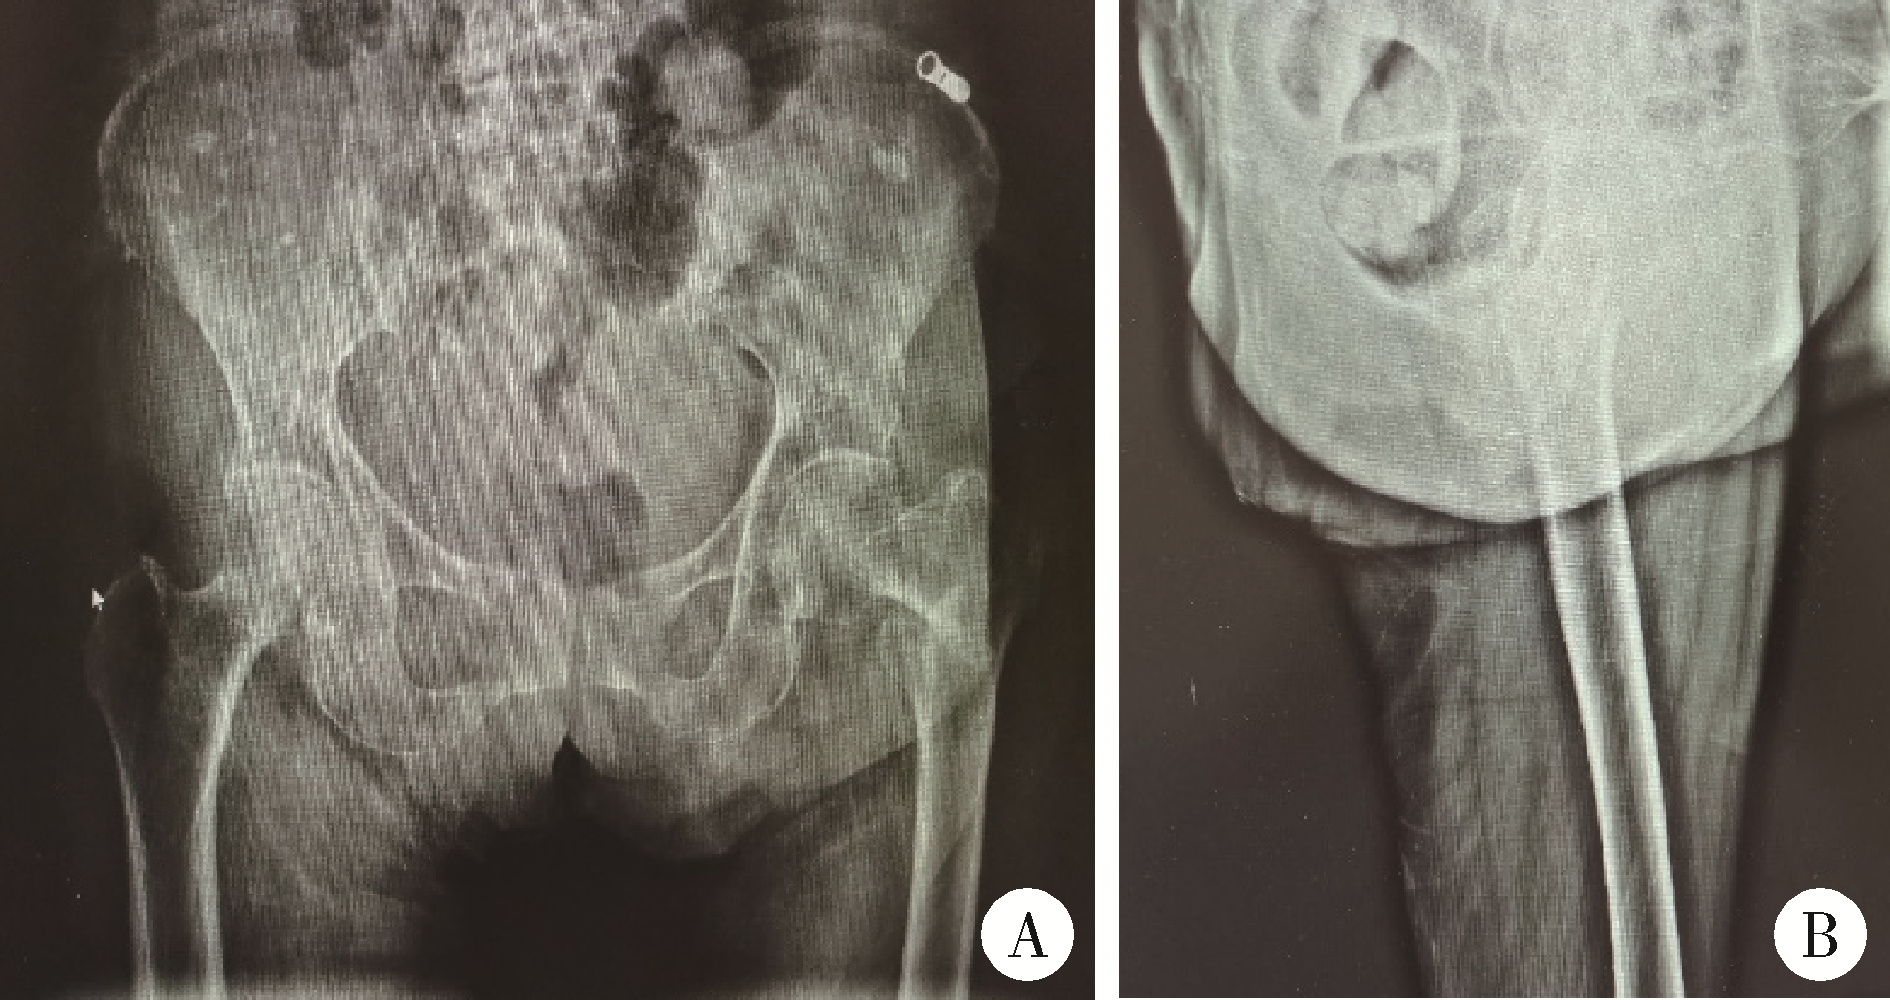

图3 患者左股骨粗隆间骨折闭合复位髓内钉内固定术后X线片

Figure 3 X-ray after closed reduction and intramedullary nail fixation of left femoral intertrochanteric fracture of patient

A, post-operative anteroposterior view of hips; B, lateral view of left hip, showed that the fracture reduction and internal fixation was satisfactory.

老年女性患者,88岁,患者2020年10月26日步行时不慎摔倒,左髋着地。于北京大学第一医院急诊查双髋X线片示左侧股骨粗隆间不稳定骨折(图 1)。查体:生命体征平稳。左髋强迫外展外旋位,左下肢短缩约2 cm。左髋局部压痛,轴向叩击痛,活动度拒查。双下肢感觉无异常,双侧足背动脉搏动可。入院后行左股骨粗隆间骨折闭合复位InterTAN髓内钉固定术,术中复位满意,过程顺利(图 2),术后复查髋关节X线片示骨折复位及内固定物位置满意(图 3)。术后次日开始骨化三醇、碳酸钙D3抗骨质疏松治疗,术后1周加用地舒单抗。术后1个半月部分负重,术后3个月可下地行走,无明显不适。2021年10月7日(术后12个月)无明显诱因出现左髋疼痛,进行性加重,逐渐出现行走困难。2022年2月28日(术后16个月)于北京大学第一医院门诊复查双髋正位X线片考虑左侧股骨颈骨折,内固定物对髋臼侧骨质有一定破坏(图 4),为行治疗收治入院。既往有高血压、腔隙性脑梗、房颤病史。查体:生命体征平稳,左髋关节周围压痛明显,无红肿,关节活动受限,疼痛明显,查体配合差。入院查血常规:白细胞计数7.1×109/L,中性粒细胞计数6.5×109/L,中性粒细胞百分比92.3%,超敏C反应蛋白4.27 mg/L,降钙素原0.02 μg/L,除外感染后行左髋关节内固定物取出加半髋关节置换术,术中未见浑浊关节液及组织液,既往股骨粗隆间骨折部位已完全愈合,新发股骨颈骨折(图 5),髋臼外上方有一处头颈螺钉切割出的缺损区,直径约1.5 cm,内有纤维瘢痕组织填充,取局部组织留取病理,送咽拭子细菌培养,培养结果阴性。术中采用骨水泥型11号股骨假体柄(长度200 mm)和外径44 mm的双极金属股骨头行半髋关节置换术,术后复查髋关节X线片(图 6),可见髋臼侧骨质密度减低。术后预防性抗感染治疗,术后1周出院,院外继续抗骨质疏松治疗。术后3个月患者反馈左髋疼痛及功能明显改善,患者及家属对治疗满意。